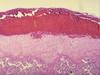

Placenta 1st trimester

edematous chorionic vili, few syncytial knots, sparse vasculature, stroma separated by 2layers—outer syncytiotrophoblast & inner cytotrophoblast